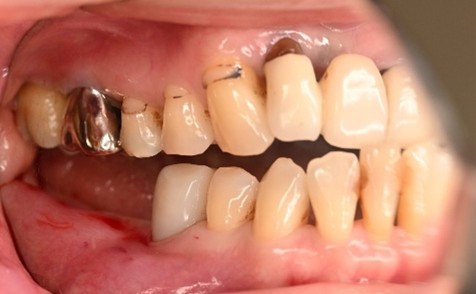

男性 Kさん 60代 (インプラント)

主訴

下の左右歯がないところに歯を入れたい。

治療内容

左右それぞれ3本歯がないところに2本ずつインプラントを埋入しました。

所感

上と下の歯の咬合接触がないすれ違い咬合です。上下義歯で対応するには最も難しいタイプの欠損状況です。治療開始前は、上下部分入れ歯が入っていましたが、入れ歯の安定が悪く、あちこちの歯茎に入れ歯が当たって痛く、満足に噛める状態ではありませんでした。上顎は、残ってる歯を活用するマグネット式総義歯を、下顎はインプラントを提案しました。上顎は、現在残っている歯の根管治療中です。上顎にマグネット式総義歯がはいれば、何でも食べられるようになります。

インプラント4本:¥363,000×4本=¥1,452,000(税込)

ポンティック2本:¥115,500×2本=¥231,000(税込)

合計:¥1,683,000(税込)

Before

▼初診時に使用していた部分入れ歯を装着したところ

▼インプラント埋入前

After

▼インプラント埋入後